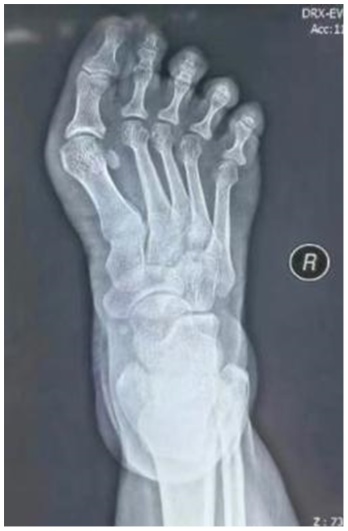

患者女,46岁。因“右足进行性行走疼痛、伴踇趾外翻畸形8月余”来我科就诊。专科检查:右侧第一跖趾关节外翻畸形(见图1(a)图1(b)),活动受限,拇囊部位压痛明显,无纵向叩击痛。第一跖趾关节松弛,活动后疼痛加重。前足功能AOFAS评分为45分,神经血管检查正常,其余肢体未见异常。既往史无特殊,检验结果未见异常。右足部X线片显示:右侧第一跖趾关节对位欠佳呈外翻改变,外翻角约33˚,第1、2跖骨间夹角约为9˚,第一近节趾骨近端可见骨质增生边尖(见图1(c))。入院诊断:右足拇外翻合并第一跖趾关节半脱位。完善相关检查后,行右足拇外翻切开截骨矫形克氏针内固定术。手术过程:麻醉生效后,患者取仰卧位,绑止血带,右下肢常规消毒铺巾,打止血带,C臂透视确认截骨位置,截骨位置靠近跖骨颈的内侧隆起处。皮肤切口:取右足背内侧第一跖趾关节处纵切口,切一长约2 cm皮肤切口。操作过程:电刀分离皮下组织至关节囊,电凝止血,切除增生关节囊,显露内侧跖趾关节,用摆据距跖骨远端2 cm处垂直于跖骨干横向截骨,将跖骨头向外侧推移,将第1根金属骨针沿远端截骨断端前内侧皮下置入并从拇趾趾甲近端内侧皮缘穿出,将布巾钳插入跖骨截骨近端髓腔,再从拇趾趾甲内侧将金属骨针置入跖骨干髓腔基底部内固定,透视确认足拇外翻畸形矫形满意,将第2根金属骨针从跖骨内侧缘距离跖骨近端截骨面1 cm处上斜形插入,从远端截骨面中点穿过,从跖骨远端外侧皮质穿出(见图1(d)图1(e)),固定截骨远端,C臂透视见拇外翻纠正,内固定位置可(见图1(g))。逐层缝合切口,以敷料固定包扎保护拇趾于中立位(见图1(f)),术后第2天复查X线(见图1(h))。术后6周来院拆除第2根金属骨针后,复查X线示恢复可(见图1(i)),术后7周来院拆除第1根金属骨针,复查X线片示恢复可(见图1(j)),术后3月我院复查足部情况(见图1(k))。

(a) (b) (c) (d)

(e) (f) (g)

(h) (i) (j) (k)

(a) (b) 术前右足外观;(c) 术前片X线片:右足中度拇外翻并第一跖趾关节半脱位;(d) 术中克氏针固定位置;(e) (f) 皮肤切口:右足背内侧第一跖趾关节处纵切口,切一长约2 cm;(g) C臂透视确认脱位复位满意,内固定位置可;(h) 术后右足正侧位x片显示:第一跖趾关节对位良好,跖骨断端对线可,轻度向内移动约1/4;(i) 术后6周患者右足部X线复查情况;(j) 术后7周右足部X线复查情况;(k) 术后3月右足部复查情况。

Figure 1. Patient’s imaging data

1. 患者影像学资料

本例患者HVA约为33˚,IMA约为9˚,属于中度拇外翻畸形,通过病例特点应用临时克氏针内固定治疗,成功地矫正了HVA角度,术中出血少,且术后未发生针道及切口感染、克氏针松动移位等并发症。术后1年随访,患者右足未出现明显疼痛,影像学复查示截骨端骨性愈合良好,无畸形复发。末次随访时HVA约为4.2˚,IMA约为4.6˚,前足功能AOFAS评分为90分,短期内取得了较满意的手术疗效。未来将进行长期随访,观察患者的远期临床疗效。